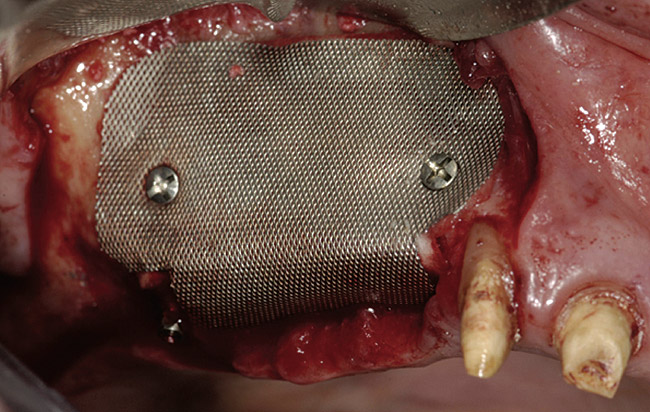

Figure 5  Titanium mesh/particulate graft complex.

Figure 5

A 16-year-old female patient with a congenitally missing maxillary right lateral incisor was referred for an implant-supported crown. Clinical and CBCT evaluation revealed both a facial and palatal bony width deficiency (Figure 2 and Figure 3). The treatment plan included the use of titanium mesh and rhBMP-2/ACS (INFUSE® Bone Graft) along with mineralized allograft (MinerOss®, BioHorizons, www.BioHorizons.com) for bony augmentation (Figure 4 and Figure 5). After 7 months, the graft was found to be well incorporated and allowed for placement of a 3.8-mm x 10.5-mm diameter root form implant that was restored 3 months later (Figure 6, Figure 7, Figure 8, Figure 9 and Figure 10).